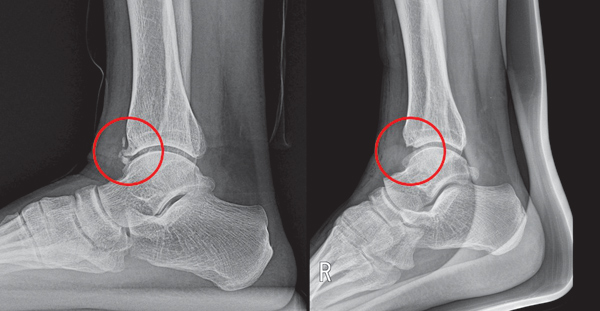

6. 발바닥 뼈 골절 또는 피로골절

- 원인: 외상이나 반복적인 충격으로 발바닥 뼈에 미세 골절 발생.

- 특징: 특정 부위의 국소적인 심한 통증, 부기.

- 위험 요인: 마라톤, 군 훈련, 과도한 체중 부하.

- 대처법: 발 고정, 체중 부하 최소화, 장기 휴식.